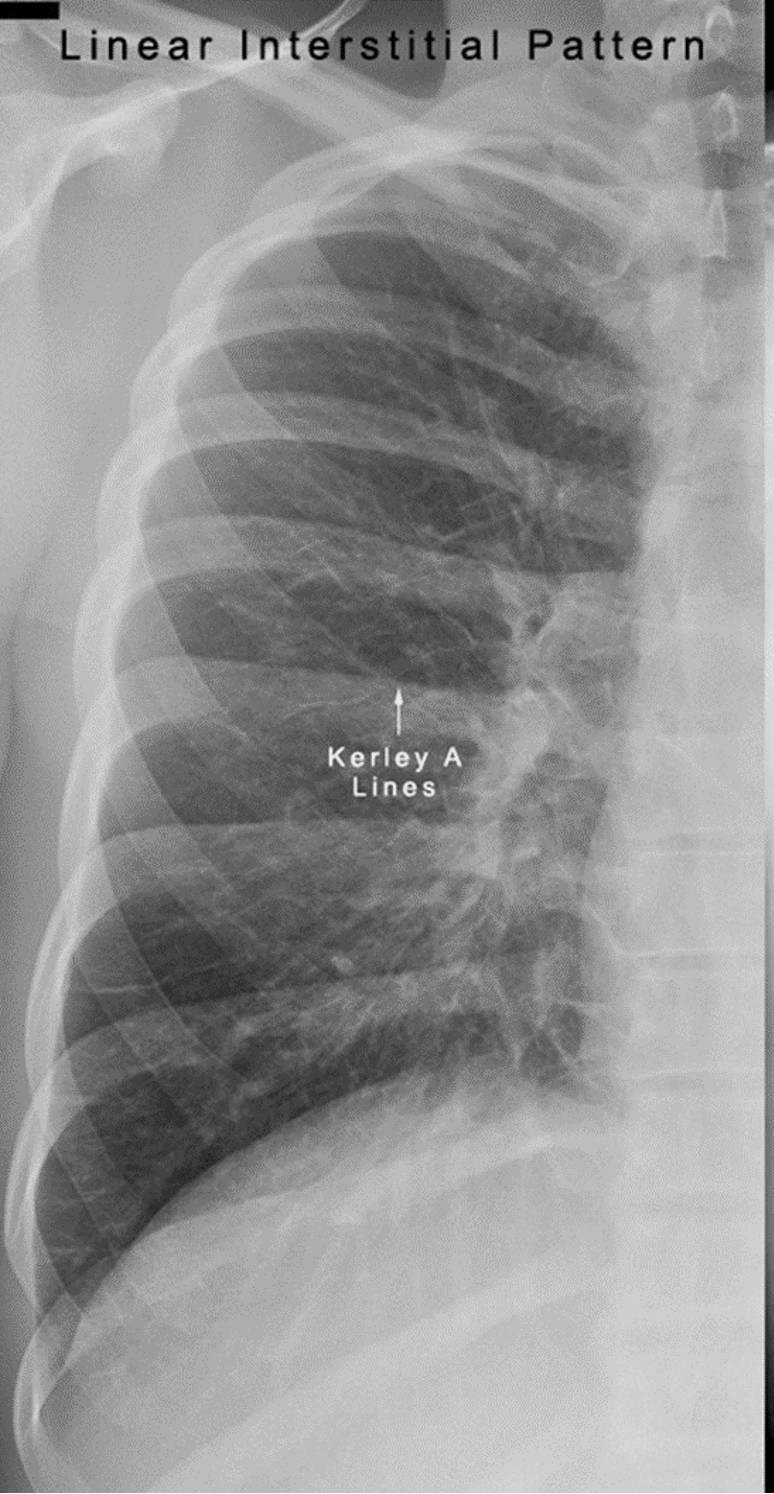

Differentiate between Kerley A vs Kerley B lines.

Kerley A: linear opacities extending from periphery to hila

Kerley B: small, horizontal, peripheral lines seen at the lung bases (represent thickened interlobular septa on CXR)

Interstitial infiltrate pattern on CXR found in patients with interstitial pulmonary edema?

Kerley lines